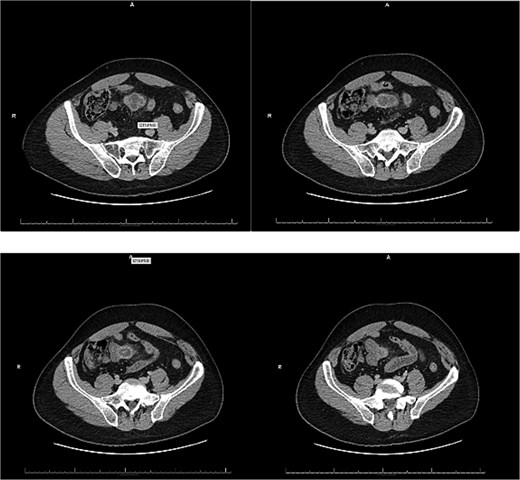

A 54-year-old male with a history of hyperlipidemia presented with several hours of worsening lower abdominal pain radiating to the right lower quadrant. He denied nausea, vomiting, diarrhea, or recent illnesses. On examination, he appeared uncomfortable, with a taut, non-distended abdomen, diffuse tenderness, and hypoactive bowel sounds. Laboratory studies revealed leukocytosis (WBC 22.37 K/μL), and an abdominal computed tomography (CT) showed a thick-walled, inflamed, blind-ending tubular structure in the midline pelvis with surrounding fat stranding and small bowel wall thickening, consistent with acute Meckel diverticulitis (Fig. 1). No bowel obstruction or fluid collection was identified. The patient was kept nothing by mouth (NPO), started on IV fluids and broad-spectrum antibiotics, and offered surgical intervention.

Patients with Meckel diverticulitis typically present with right lower quadrant pain, fever, and leukocytosis. Additionally, CT imaging reveals a blind-ended pouch with mural thickness, mesenteric inflammation, or air-fluid levels [8]. In our patient, CT findings were suggestive of acute Meckel diverticulitis but did not indicate perforation or abscess formation. However, laparoscopy revealed purulent peritonitis and abscesses, confirming the presence of complicated diverticulitis with probable perforation.